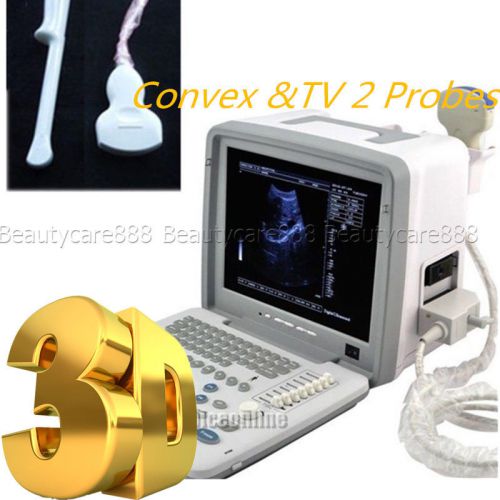

Full Digital Portable Ultrasound Scanner Machine +Convex and TV probes free 3D

FDA CE 3D Full Digital Portable Ultrasound Scanner Machine +Convex+TV 2 Probes